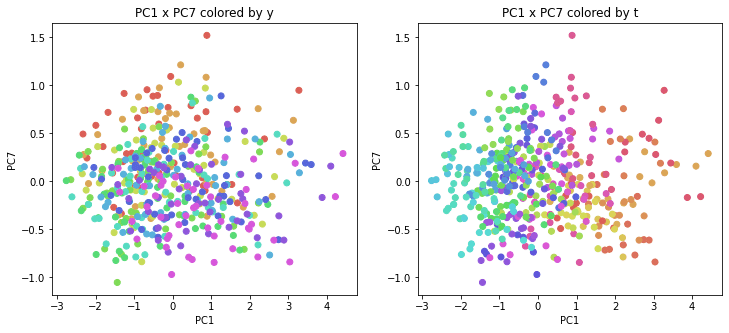

PCAの結果の第n主成分をPCnと表記します。

医療費データの場合と同様に、PCAの結果を見やすく表示するため、seabornのカラーパレットを使って、年月別、都道府県別に色分けして図示してみます(左側が年月別に色分け、右側が都道府県別に色分け)。PC1~PC8まで表示しました。

医療費データの場合ほどはっきりとはしていませんが、PC2が概ね時間の経過を表す成分で、残りの成分が時点によって変わらない地域の特徴を表す成分となっているようです。

また、PC1×PC3を見ると、47沖縄が他の都道府県からかなり離れたところに位置しており、沖縄の地域差が際立っているのが分かります。これは、以前別の記事で年齢階級のない健診データでPCAを実行した場合と似た結果となっています。

今回は、医療費データと同様に、健診データ240次元についてPCAを実行してみました。PCAの結果、医療費データの場合ほどはっきりしとはしていませんが、第2主成分が概ね時間の経過を表す成分で、時間軸に沿った全体的な動き(全国的な動き)を表しており、それ以外の成分が地域の特徴を表す成分で、この10年間あまり変わっていないことがわかりました。